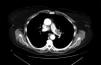

Mujer de 68 años con antecedentes de neoplasia de colon, tiroidea y carcinoma in situ en epiglotis. En junio de 2011 fue diagnosticada mediante fibrobroncoscopia de carcinoma microcítico de pulmón en el segmento anterior de lóbulo superior izquierdo (LSI) tratado con 6 ciclos de CDDP-VP-16 y radioterapia (RT) torácica y holocraneal (acabando el tratamiento en noviembre de 2011). En el estudio radiológico se observó imagen ocupante de espacio en la arteria pulmonar izquierda sugestiva de trombo intramural (fig. 1), por lo que se realizó tratamiento con anticoagulante durante un año.

En los controles radiológicos se observó progresión de la lesión intraarterial, valorándose la posibilidad de un origen tumoral. Debido a la localización de la lesión y la imposibilidad de tomar muestra histológica a este nivel, se decidió intervención quirúrgica diagnóstico-terapéutica. Se realizó neumonectomía izquierda con sección arterial intrapericárdica con márgenes libres de tumor. El resultado de anatomía patológica fue metástasis de carcinoma microcítico de pulmón con márgenes de resección libres. En el postoperatorio no presentó complicaciones intratorácicas. Actualmente se encuentra en seguimiento por oncología médica sin datos de recidiva de la enfermedad pulmonar.